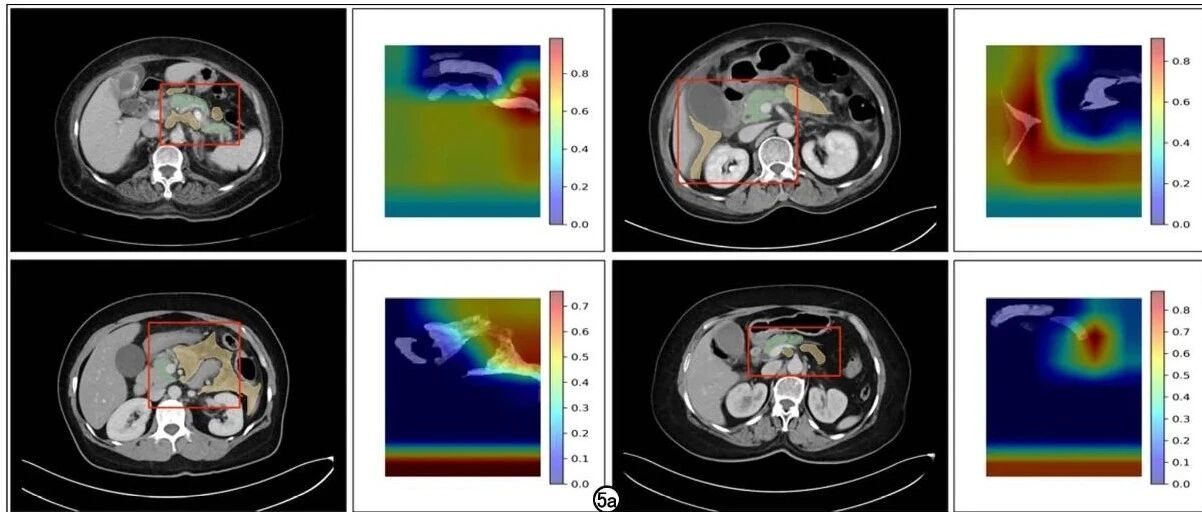

基于深度学习的早期急性胰腺炎严重程度分级预测 放射学实践 · 公众号 · 医学 · 9 月前 · |